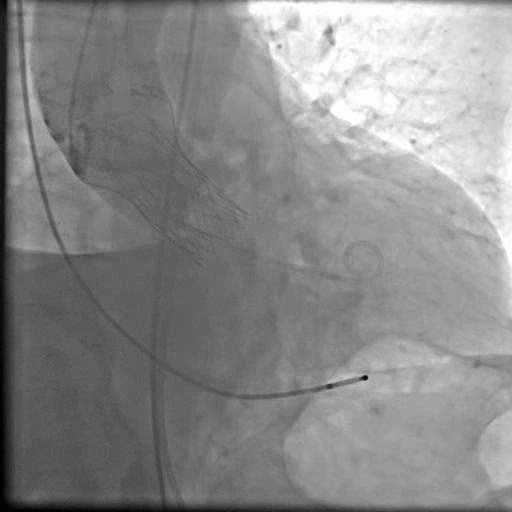

TAVR手术是一种非侵入性的介入治疗方法,通过导管将人工瓣膜送达到患者的主动脉瓣位置,取代受损的瓣膜。这种手术方法不需要进行开胸手术,只需通过小切口或血管插管即可完成,大大降低了手术风险和恢复时间。经过杨先生及其家人的商议,他决定住院接受这种治疗方法。

在手术当天,杨先生被送往手术室进行TAVR手术。这种手术需要通过切口或血管插管将人工瓣膜送达到主动脉瓣位置。通过导管的引导下,人工瓣膜被展开并取代受损的瓣膜,恢复了心脏正常的血液流动。手术非常成功,杨先生的主动脉瓣问题得到解决。